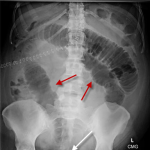

| B | • Bowel gas | • 3,6,9 rule - small bowel <3cm, large bowel <6cm, caecum and sigmoid <9cm |

| B | • Bones | • ribs, lumbar vertebrae, sacrum, coccyx, pelvis and proximal femurs |

| C | • Calcification • artifacts | • arterial Ca++, phelobliths, calculi • clips, tubes, implants |